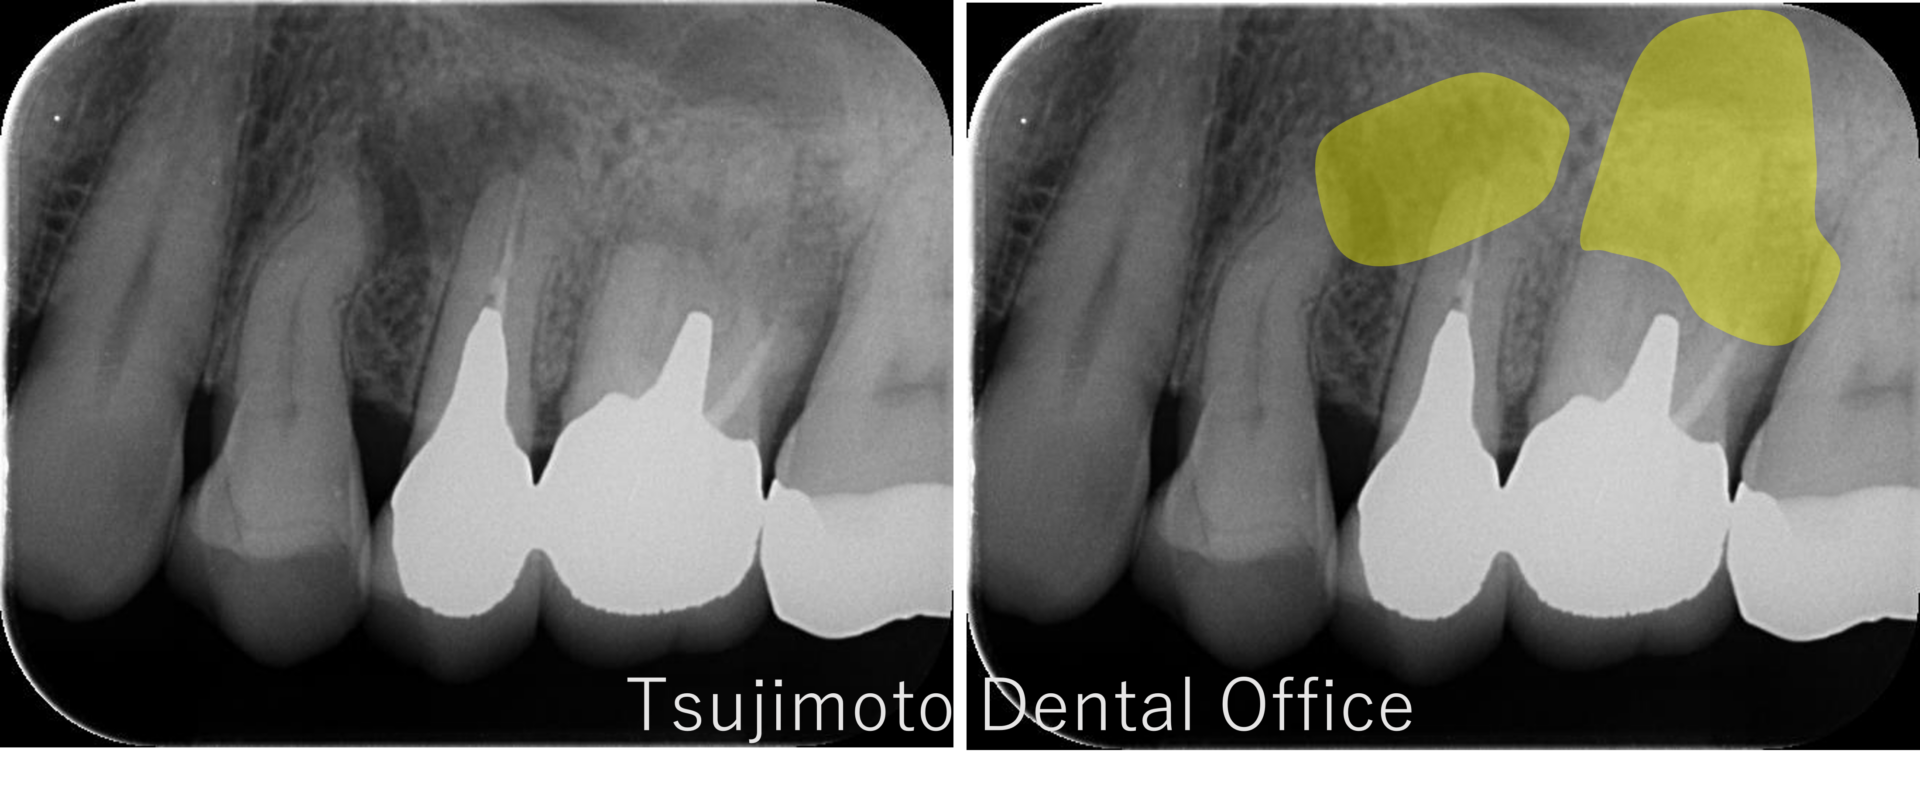

根管治療

大きな病変が出来ている大臼歯の根管治療

Before

After

| 年齢 | 58歳 |

|---|---|

| 性別 | 女性 |

| 治療期間 | 約3カ月(冠除去~根管治療治療3回、その他3回) |

| 治療方法 | マイクロスコープを使用した根管治療、レジン築造、e-maxクラウン |

| 治療費用 | 約40万 |